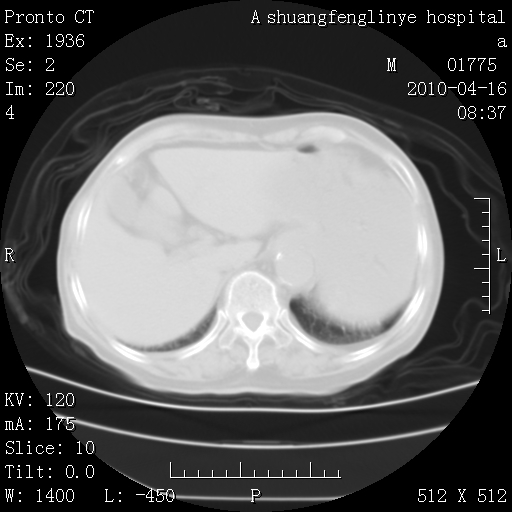

标题: CT25784:咳痰、请会诊!结核? [打印本页]

标题: CT25784:咳痰、请会诊!结核?

陈旧性结核,胃腔扩大,脾脏受压后移

慢支肺气肿,左上陈旧性结核,主动脉冠脉钙化

典型 夹层动脉瘤。 内膜瓣钙化移位

1)左肺上叶结核(纤维、增殖病灶)。2)冠状动脉及主动脉钙化。

1)左肺上叶结核(纤维、增殖病灶)。2)冠状动脉及主动脉钙化。肺动脉高压